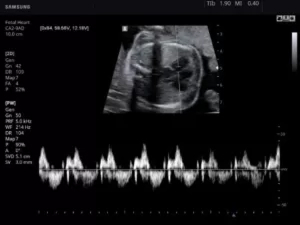

Режим PW (Pulsed Wave, спектральный, или импульсно-волновой)

В данном режиме ультразвук испускается сериями им­пульсов, которые, отразившись от эритроцитов, последовательно принимаются этим же датчиком. Также имеется воз­можность избирательного измерения скорости кровотока в отдельном сосуде.

Минусами PW-доплерографии являются невозможность исследования высоких скоростей потока в сосу­дах, расположенных на большой глубине, и вероятность искажения спектра скоростей течения жидкости, когда высокоскоростной кровоток ошибочно отображается как низко­скоростной.

28.jpg

Рис.4. Сердце плода в PW-режиме.